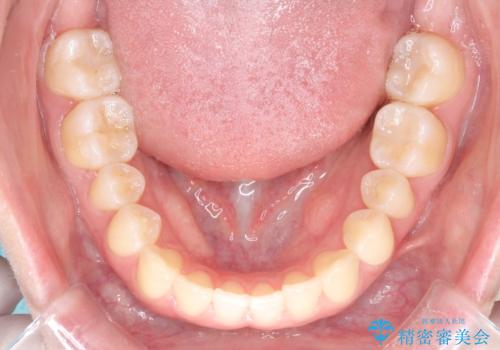

- 前歯のガタツキが気になるとのことで来院されました。

ワイヤー矯正とインビザライン矯正を併用することによって、治療期間の短縮と、より良い仕上がりを目指す治療を選択することとしました。

インビザライン(アライナー)矯正とワイヤー矯正のそれぞれの利点を生かした治療を行い、綺麗な歯並びになりました。